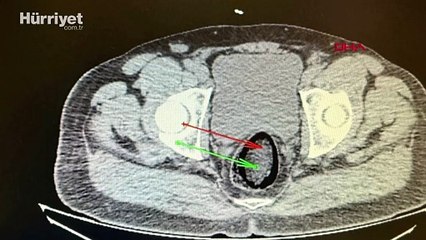

Kars'ta, polisin durdurduğu yolcu otobüsünde hareketinden şüphelenilen İran uyruklu F.H. adlı erkek yolcunun hastanede çekilen röntgeninde, makatında uyuşturucu tespit edildi. Uyuşturucu cerrahi operasyonla çıkarılırken, şüpheli tutuklandı.